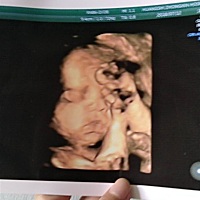

6月28,刨腹小公主一枚,开心满足幸福爆棚。